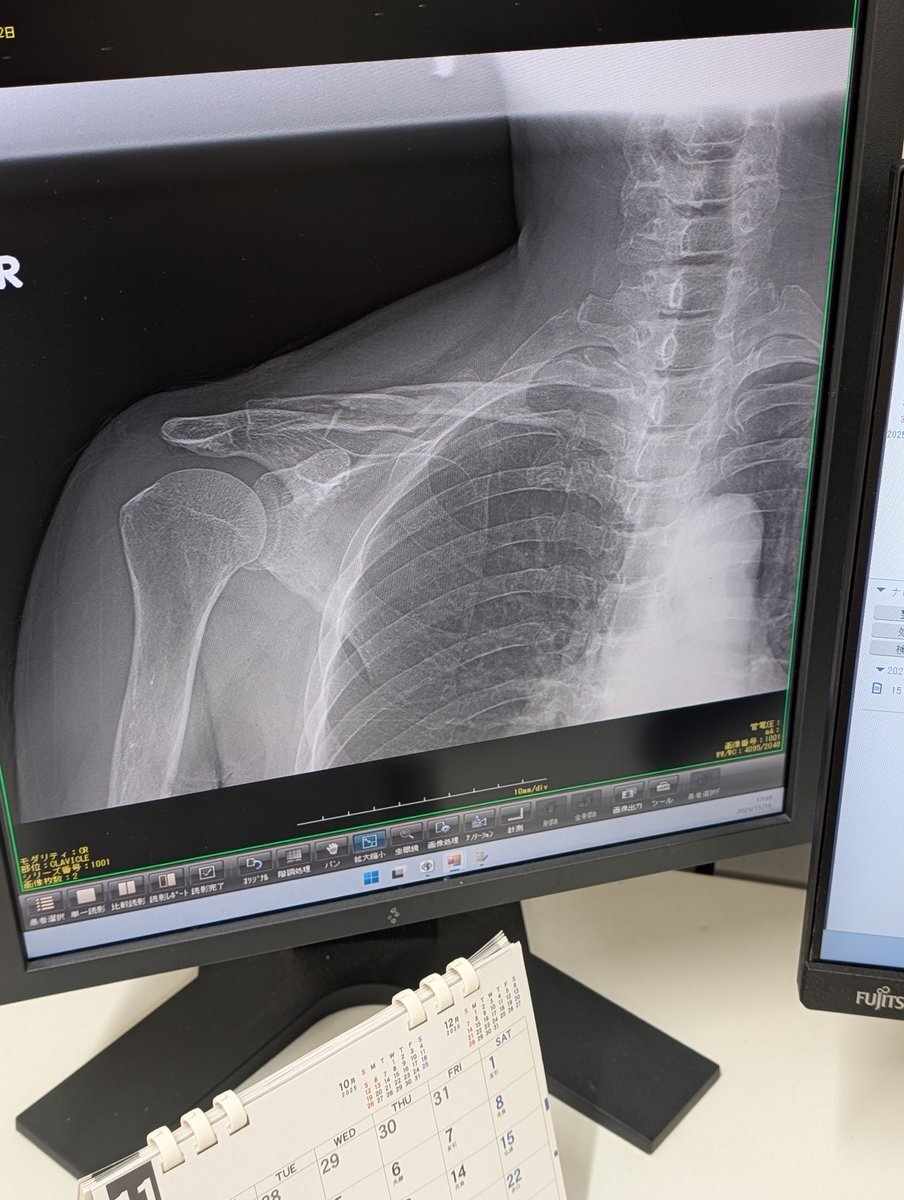

#またまたやってしまった #鎖骨骨折 #ウェイン様月間中に またやってしまった?! 今度は鎖骨骨折💦 医者“やぁ見事に骨折してるなぁ” 本当に痛みが半端でない 立ってても寝ても痛い 痛がるわたしに家族は冷たい1言 それでアメリカ行けるのかい?! あぁ~ウェイン様が痛みと共に 遠ざかります😭 pic.x.com/6EYdC1dzMp